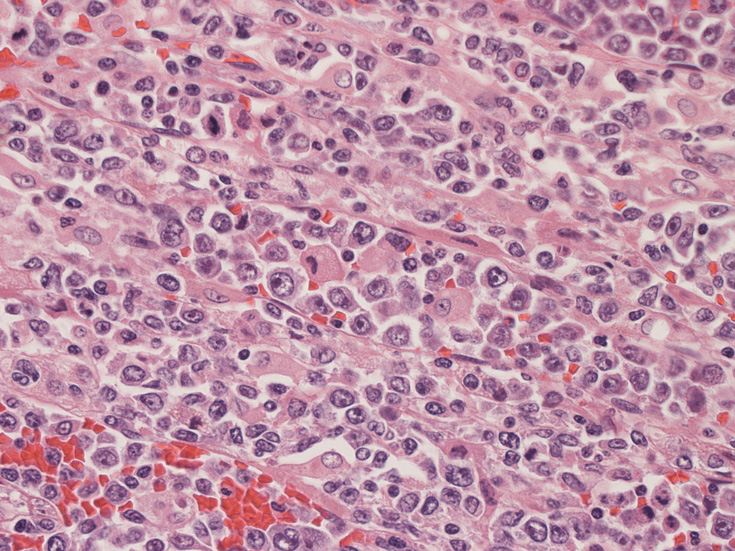

骨髄の組織所見

肺組織所見

血管内異常リンパ球増殖症例であるが、細胞はCD20陰性, CD79a陰性, CD3陰性である。BCR, TCR遺伝子再構成も認められなかった。(細胞量の関係もあるか?). EBER-ISHは周囲小型リンパ球に陽性所見を認めたが腫瘍細胞はEBER(-)であった。